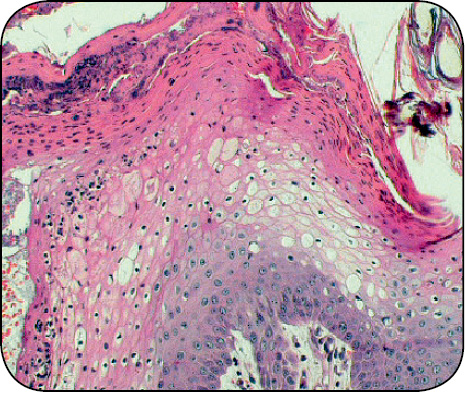

W oparciu o diagnostykę różnicową przeprowadzono szereg badań (tab. 1). Badanie cytologiczne skóry wykazało ropne zakażenie ziarniakami. W posiewach wyhodowano Staphylococcus intermedium. Badanie biochemiczne surowicy wykazało obniżony poziom mocznika oraz lekko podwyższone AP i ALT (tab. 2). W badaniu ultrasonograficznym jamy brzusznej, w wątrobie widoczne były obszary o średnicy do 15 mm otoczone przez mniej echogenne pasma, co przypominało wyglądem ser szwajcarski (ryc. 4), s. 30. Dodatkowo pobrano wiele próbek – bioptatów z chorobowo zmienionych miejsc na skórze. Naskórek był przerośnięty ze znacznym rogowaceniem warstwy powierzchownej o charakterze parakeratozy, z wakuolizacją keratynocytów w warstwie kolczystej i rozrostem komórek w warstwie podstawnej naskórka (ryc. 5, 6), s. 30. Opisanym zmianom towarzyszył rozproszony naciek komórek zapalnych (limfocytów i komórek plazmatycznych). Na tej podstawie postawiono wówczas rozpoznanie MEN, wtórnego ropnego zapalenia skóry oraz wyrównanego zapalenia wsierdzia zastawki mitralnej.